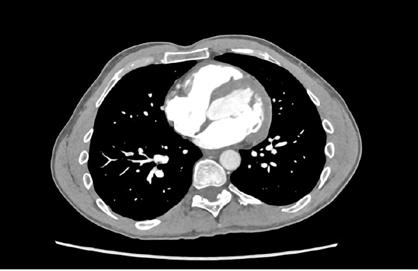

Se realizó una tomografía computarizada (TC) con contraste de forma emergente, que mostró una disección aórtica iatrogénica tipo A focal de origen en la zona 0 del cayado con extensión al tronco braquiocefálico derecho (1) sin afectar al resto de troncos supra-aórticos, cayado o aorta descendente (Figuras 1 y 2); además del hematoma

Figuras 1 y 2: Prótesis aórtica migrada y disección aórtica focal tipo A, de origen en la curvatura menor del arco aórtico (zona 0) hasta la bifurcación de la arteria braquiocefálica derecha; sin afectación de del resto de troncos supra-aórticos, del resto del cayado aórtico o de la aorta descendente.